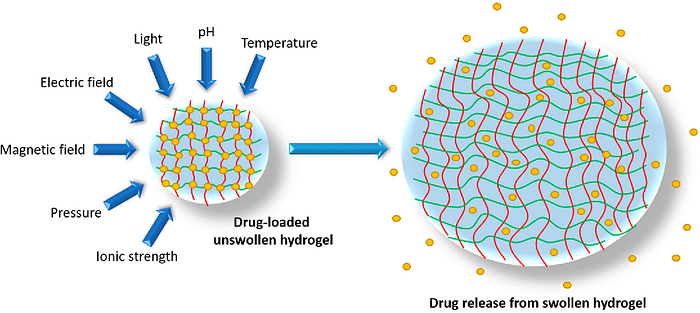

Now that we understand the importance of hydrogels, lets return to nanogels. A nanogels characteristics, such as size, charge, porosity, amphiphilicity, softness, and degradability, can be fine-tuned by varying their chemical composition. They can be designed in a spherical shape or in a more porous structure, with holes in their shape. From a drug delivery perspective, this essentially allows us to design the system based on how we want the drug to be released. Based on the structure, drugs can be released in different orders. For example, in a spherical shape, the outermost contained drug would be released first; however, in a porous structure, you could theoretically have the innermost structure released first. The porous structure is sort of like Swiss cheese in that there are ways to get to the middle of the structure, allowing you to theoretically release drugs from the inside out.

- Nanogels not only protect the cargo from degradation and elimination but also participate actively in the delivery process due to their characteristic properties, like stimuli-responsive behaviour (responding to changes in the body) softness and swelling to help achieve a controlled, triggered response at the target site. Protecting the cargo is important to ensure the drug isn’t accidentally released in the wrong place. Softness is also critical to ensure the drug delivery system does not scratch or harm internal organs. Finally, as will be discussed later, this stimuli-responsive behavior is key as the hydrogel can essentially be programmed to release the drug based on certain conditions in the body.

- Their very rapid response to a change in environmental conditions. They can adapt to different pH, temperature, and other characteristics in the body, which is important given how varying the climate is and we can’t control what happens in vivo. The responsiveness of nanogels to the external physical or chemical signals can also be tightly regulated by controlling the structure of the materials used for the preparation of the nanogels.

For the crosslinking agent, we will use 1,4-butanediol diglycidyl ether (BDDE), which has gained approval from the Food and Drug Administration (FDA). We chose BDDE because it has shown the most significant swelling response to pH changes, making it promising for various biomedical applications where biodegradability and biocompatibility are crucial. Furthermore, the swelling of nanogels in an aqueous environment allows these cargos to be released more efficiently into the surrounding environment.

Once inside, the nanogel will break apart from the red blood cell and travel to the tumor site. Because hyaluronic acid has a high affinity to cancer cells expressing the CD44 receptor, they have a great desire to find these cells and bind to them. Once it reaches the tumor, these nanogels will be engineered to be sensitive to hypoxic (low oxygen) and highly acidic conditions, which are commonly found within and on the surface of glioblastoma tumors. Thus, when the nanogel encounters this environment it will slowly degrade and slowly release the drug payload. Sustained drug release, slow release of a drug at a programmed rate to deliver the drug over a prolonged period of time, is extremely advantageous, mainly because it reduces the number of doses, lowering expenses and improving patient compliance. Furthermore, sustained drug release also decreases side effects and provides the ability to maintain a constant level of medication within the body. Releasing drugs directly in the tumor (otherwise known as targeted drug delivery) leads to greatly enhanced therapeutic efficacy because the drug is already at the site of action, making it easier to eliminate cancer cells while also not destroying healthy cells. Furthermore, targeted drug delivery can expand the pool of drugs that can be safely and effectively administered, enabling the development of novel therapies for previously untreatable conditions.

Being precise with the amount of crosslinking agent is also critical. If the amount of crosslinking agent used is too small, then the physical interaction between polymer bonds breaks easily, causing the nanogel to become water soluble and could result in it dissolving too early. However, if too much crosslinking agent is used, then a high crosslinking degree causes a low swelling degree of hydrogel, which, as discussed, makes the drug release process a lot harder.

In a study testing chemical crosslinking using BDDE, high crosslinking yields of over 90% were confirmed for all samples except when a 1:10 hyaluronic acid to BDDE molecular weight ratio was used. In these cases, the excess BDDE caused problems due to a large amount of unreacted BDDE, which limits the effectiveness (reduced solubility, improved elasticity, and enhanced mechanical strength and stability) of using high concentrations of BDDE in making hyaluronic acid nanogels. It was also found that using a low amount of BDDE significantly impacted the size of the nanogels, regardless of the HA’s molecular weight. Nanogels made with just 0.2 equivalents of BDDE had much larger particle sizes compared to those made with higher ratios of hyaluronic acid to BDDE (1:1 and 1:10). These low-crosslinked nanogels (1:0.2 hyaluronic acid:BDDE) also displayed better swelling properties, meaning they could absorb more water and expand more when the pH changed or when transitioning from dry to wet states. Thus, we now encounter a situation where we need to evaluate the trade-offs of using a high amount of BDDE versus a low amount.